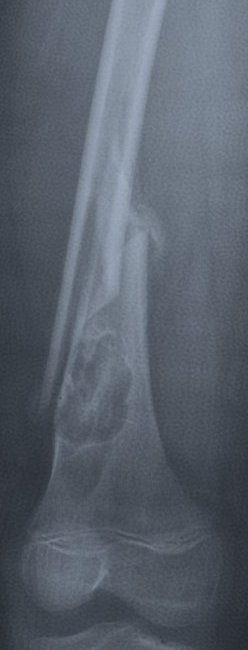

Kemiğin duvarından gelişebilen iyi huylu bir tümör de “fibröz kortikal defekt”tir. Nadiren ağrı yapar yada kemiğin duvarını zayıflatabilir. Çoğu zaman başka bir nedenle çekilen röntgende tesadüfen saptanır (resim-15). Büyük oranda ameliyat gerektirmez ve kendiliğinden iyileşme gösterir. Ancak fazlaca büyüyüp kemiğin büyük kısmını etkilemişse ameliyatla temizlenmesi gerekir. Aksi halde “patolojik kırık” dediğimiz kemiğin aşırı zayıflamasına bağlı kırık durumu gelişebilecektir (resim-16). “Non-ossifiye fibrom” içinde benzer şeyler söylemek mümkündür (resim-17).

Patolojik kırıklar her kemik tümörü zemininde gelişebilir. Kemik duvarlarının tümör nedeniyle aşırı zayıflaması nedeniyle ortaya çıkar. Kemik sarkomlarında meydana gelirse tedavi çok zorlaşır. Çünkü bu durumda kötü huylu olan tümör hücreleri her yöne yayılır ve olay çok daha kompleks bir hale gelir. İyi huylu kemik tümörlerinde de aynı durum gözlenebilir. Bu durumda da tedavi daha kompleks hale gelecektir.